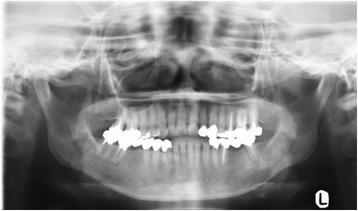

CASE PRESENTATION

In this report, we present the case of a 58-year-old Japanese woman with osteosarcoma of the mandible that was treated with radical surgery combined with neoadjuvant and adjuvant chemotherapy. Because the tumor showed rapid growth during neoadjuvant chemotherapy, neoadjuvant chemotherapy was suspended and surgical resection was performed, followed by adjuvant chemotherapy. No evidence of local recurrence and distal metastasis was found 14 months after initial treatment. Local control is considered a principal prognostic factor for head and neck osteosarcoma.

在本报告中,我们介绍了一名58岁日本女性下颌骨肉瘤患者的病例,该患者接受了根治性手术联合新辅助化疗和辅助化疗。由于肿瘤在新辅助化疗期间生长迅速,新辅助化疗暂停并进行了手术切除,随后进行辅助化疗。初始治疗14个月后未发现局部复发和远处转移迹象。局部控制被认为是头颈部骨肉瘤的主要预后因素。